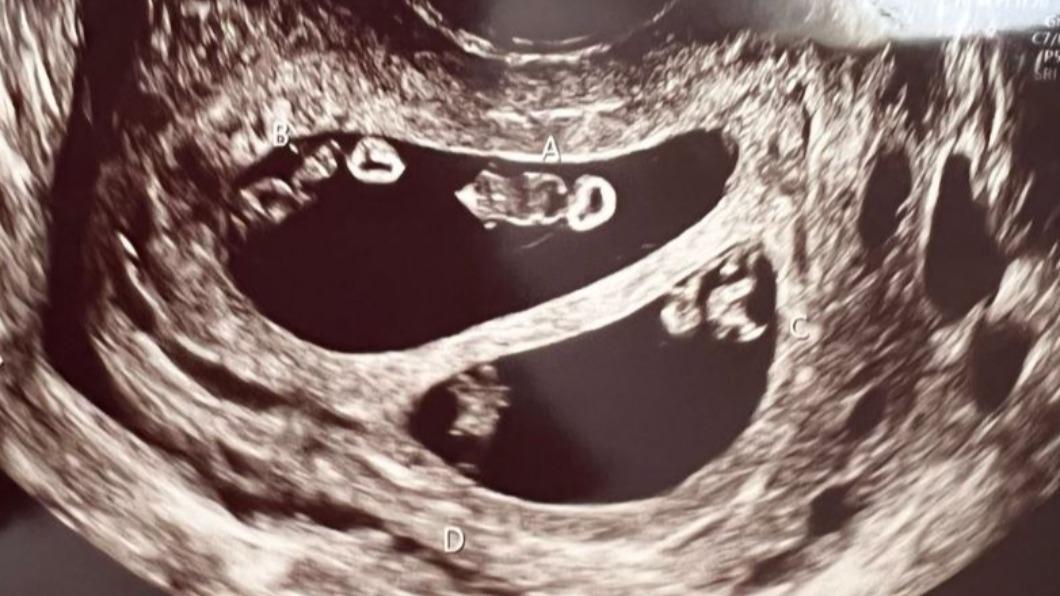

醫生在照超音波時發現驚人景象,艾希莉本來以為自己是懷著一對雙胞胎寶寶,沒想到醫生疑惑的看著螢幕好久,又走出房間請同事一起來觀察,最後才確定她竟然懷上了2對同卵雙胞胎,分別為2男2女,而醫師也解釋這狀況在醫學上發生機率僅7千萬分之一,根本就像是中了一張大樂透般不可思議!

(圖片來源:People)